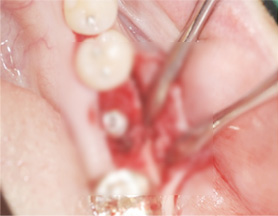

임플란트 식립

인공뼈 및 가가골 이식 (뼈 이식)

뼈의 재생을 유도 (골유도재생술)

잇몸 봉합 (3~5개월 후 완성)

아래턱 어금니 발치 후 장시간 방치하여 잇몸 뼈 소실이 심한 상태로 내원. 뼈 이식 후 임프란트를 식립하였습니다.

잇몸 뼈 소실이 심한 상태로 내원

뼈 이식 후 치조골 밀도가 높아진 모습